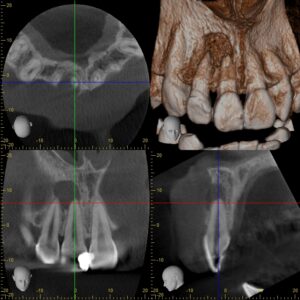

初診時CT画像。根尖部に境界明瞭な直径1㎝ほどの黒いX線透過像を認める。虫歯治療後の歯髄壊死および根尖性歯周炎と診断し、感染根管治療を行うこととした。